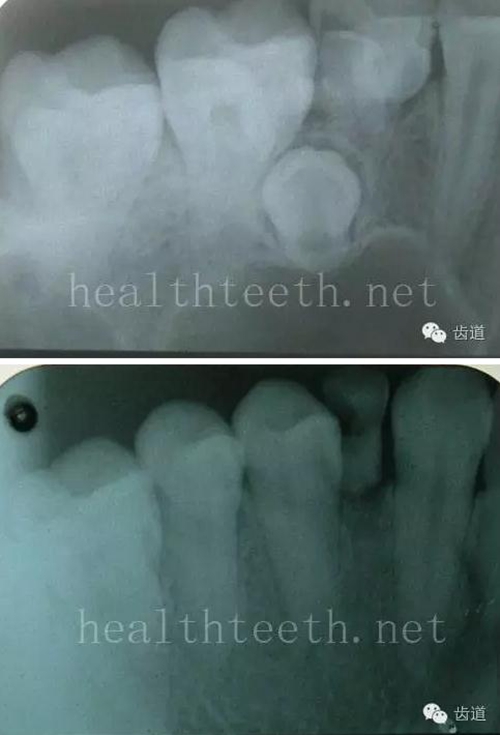

二、牙周組織病

牙片顯示牙槽骨的垂直吸收

11.jpg

外院做的牙周固定,牙片顯示牙槽骨的水平吸收